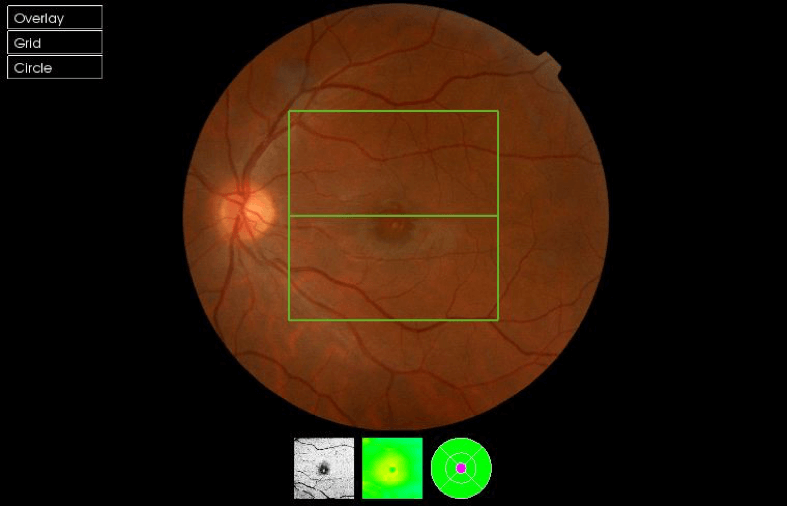

Actualmente podemos caracterizar las lesiones mediante las pruebas de imagen que aportan valoración cuantitativa y cualitativa. Es interesante, adicionalmente a la exploración funduscópica estudiar las lesiones mediante retinografía, OCT, angio-OCT, autofluorescencia, microperimetría y oftalmoscopía láser confocal(SLO). Todas ellas aportan información complementaria en el estudio, diagnóstico y seguimiento de las lesiones. A continuación se muestran retinografías y OCTs de un caso de retinopatía solar y un agujero macular producido por la acción de un láser en una discoteca ( Figuras 1,2,3,4)

Figuras 3 y 4. Agujero macular monocular producida por la acción de un láser en una discoteca en varón de 27 años, agudeza visual en el ojo afecto de 0.1.

Debido a que la tecnología láser se ha vuelto fácilmente disponible para su uso en laboratorios científicos, medicina, ocio, punteros láser y con fines militares, ha habido un aumento en los casos de lesión retiniana.El láser es una luz coherente colimada, que emite luz entre los 400-1400 nanómetros que puede producir destrucción tisular y por tanto afectación permanente e irreversible de la visión.2,13